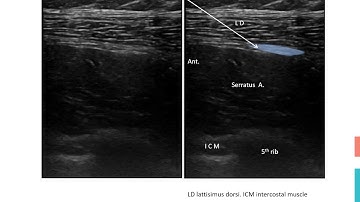

SERRATUS ANTERIOR PLANE BLOCK with Landmark Guided Technique: SIMPLIFYING NERVE BLOCKS (SNB) BLOCK 5